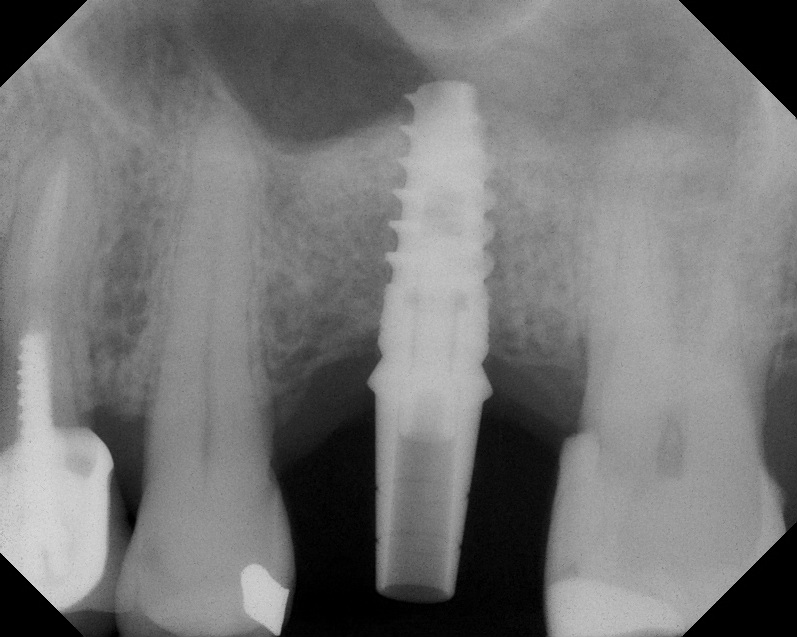

A 74-year-old man presented with only about 2 mm to 3 mm of native bone below the sinus in the No. 14 position (Figure 13). The composite graft used was an approximately 50:50 mixture of DFDBA (Bio-Oss®, Geistlich Biomaterials, www.bio-oss.com) with the addition of about 40% calcium sulfate by volume (Figure 14). The implant placed (Figure 15) was a 10-mm long, rough-surfaced, platform-shifting implant (tapered 4.2 mm to 2.8 mm), and the sinus was raised about 8 mm. The postoperative radiograph taken at 4 months (Figure 16) showed some shrinkage of the graft, but no demarcation of the old sinus floor in the area.

Case 1. Preoperative radiograph showing a ridge height of about 2 mm to 3 mm in the No. 14 position.

Fig. 13

Radiograph of sinus composite bone augmentation in the No. 14 position.

Fig. 14

Radiograph of implant No. 14 with sinus augmentation, day of placement. The floor

of the sinus has been raised about 7 mm to 8 mm.

Fig. 15

A 4-month radiograph with the abutment No. 14 in place. Note the ill-defined old sinus floor.

Fig. 16